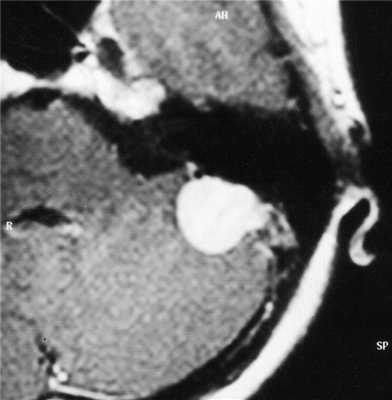

(а) Бесконтрастная КТ, аксиальный срез: у мужчины 33 лет с длительным анамнезом судорожных приступов в верхне-задней части правой теменной доли визуализируется кальцифицированное объемное образование, повторяющее ход извилин.

(б) MPT, FLAIR, аксиальный срез: у того же пациента в структуре коры визуализируется гипоинтенсивное объемное образование.

2. КТ при менингоангиоматозе:

• Бесконтрастная КТ:

о Одиночное гиперденсное, часто кальцифицированное объемное образование:

- Линейный, гиральный или узловой характер Са++

о Обнаруживаются случайно: кровоизлияния и кисты

о Масс-эффект отсутствует или не определяется

• КТ с контрастированием:

о Контрастирование низкоинтенсивное или отсутствует